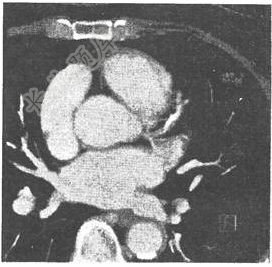

- 单项选择题患者,男,58岁,胸骨后阵发性疼痛半年余,透视见心影稍大,CT片如图,最可能的诊断是( )。

A、慢性肺源性心脏病

B、缩窄性心包炎

C、高血压性心脏病

D、冠状动脉粥样硬化性心脏病

E、风湿性心脏病二尖瓣狭窄